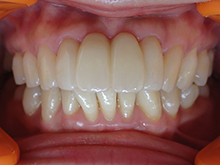

オールセラミックス

金属を使わずに全てセラミックを使用し、光の透過性を上げる事により自然な白い歯に回復させる方法です。

現在では土台から白い材質(ファイバーポストなど)の物を使用することにより、さらに透明感が増し天然歯に近似しています。

オールセラミックは近年進化を遂げており、強度や接着性がかなり改善され、審美的にとても優れたものと成って来ております。

オールセラミックにも色んな種類がありますが、当院ではe-max(二ケイ酸リチウムガラスセラミック、)ジルコニアセラミックスを採用しています。

症 例